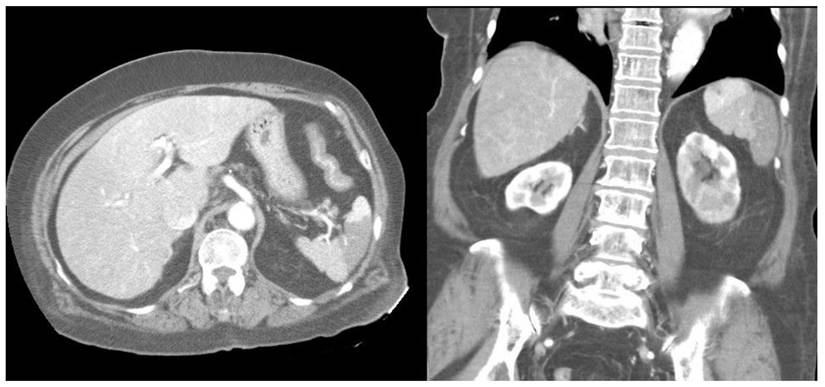

Furthermore, compared with survivors, the non-survivors exhibited significantly higher rates of left-sided pleural effusion, peri-splenic ascites, multiple or total infarction, main portal vein thrombosis, and splenic vein thrombosis on CT imaging. Co-infarctions most commonly involved the kidneys, brain, and intestines. At least one organ co-infarction occurred in 30.6% of cases, while 11.5% experienced two or more, but no significant group differences were observed (Table S4). Figure 2 shows concurrent splenic and left renal infarction, whereas Figure 3 shows splenic infarction with portal vein thrombosis and ascites in a patient with hepatocellular carcinoma.

Figure 3

Splenic infarction in a patient with hepatocellular carcinoma. Contrast-enhanced abdominal CT reveals a wedge-shaped splenic hypodensity consistent with infarction, an ill-defined heterogeneous hypodense mass in the right hepatic lobe, portal vein thrombosis, and ascites.